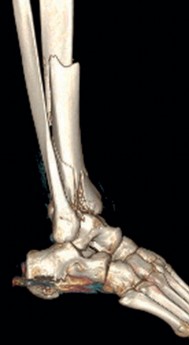

The management of complex tibial shaft fractures with extension into the distal articular surface (the tibial plafond or pilon) represents one of the most formidable challenges in orthopedic traumatology. These injuries typically result from high-energy mechanisms, such as a fall from a significant height or a motor vehicle collision, where axial loading forces are combined with severe rotational and shear vectors. The classic presentation, as highlighted in our index case of a 26-year-old male who fell 3 meters into a hole, involves not only catastrophic bony disruption but also devastating injury to the surrounding soft tissue envelope. The delicate nature of the soft tissues in the distal third of the leg, characterized by sparse muscular coverage and a precarious vascular supply, dictates the entire trajectory of clinical decision-making.

When a diaphyseal fracture propagates into the distal articular block, the injury transcends the typical treatment algorithms reserved for isolated tibial shaft fractures. Intramedullary nailing, the gold standard for diaphyseal fractures, becomes fraught with complications such as articular malreduction, propagation of intra-articular fracture lines, and inadequate distal fixation. Therefore, plate fixation—often utilizing minimally invasive percutaneous plate osteosynthesis (MIPPO) techniques—emerges as the primary definitive treatment modality. In the setting of an AO/OTA 43C3.3 fracture, where the articular surface is multifragmentary and completely dissociated from the diaphysis, the surgeon must meticulously reconstruct the joint surface before bridging the diaphyseal segment.

Pre-operative planning is the cornerstone of successful execution in complex pilon-variant tibial shaft fractures. The surgeon must transition from a conceptual understanding of the injury to a concrete, step-by-step surgical blueprint. This begins with high-quality orthogonal radiographs of the entire tibia, ankle, and knee. However, plain films drastically underestimate the degree of articular comminution and central impaction. A fine-cut computed tomography (CT) scan with 2D multiplanar reformats (coronal and sagittal) and 3D surface rendering is absolutely mandatory.

Image

The CT scan allows the surgeon to map the fracture lines, identify the primary articular fragments (Chaput, Volkmann, medial malleolus), and quantify the degree of central die-punch impaction. In an AO/OTA 43C3.3 fracture, where no articular fragment is in continuity with the diaphysis, the surgeon must plan the sequence of reduction. Typically, the fibula is addressed first to restore lateral column length and rotation, provided the fibular fracture is not located at the level of the syndesmosis where fixation might interfere with the lateral surgical approach to the tibia.